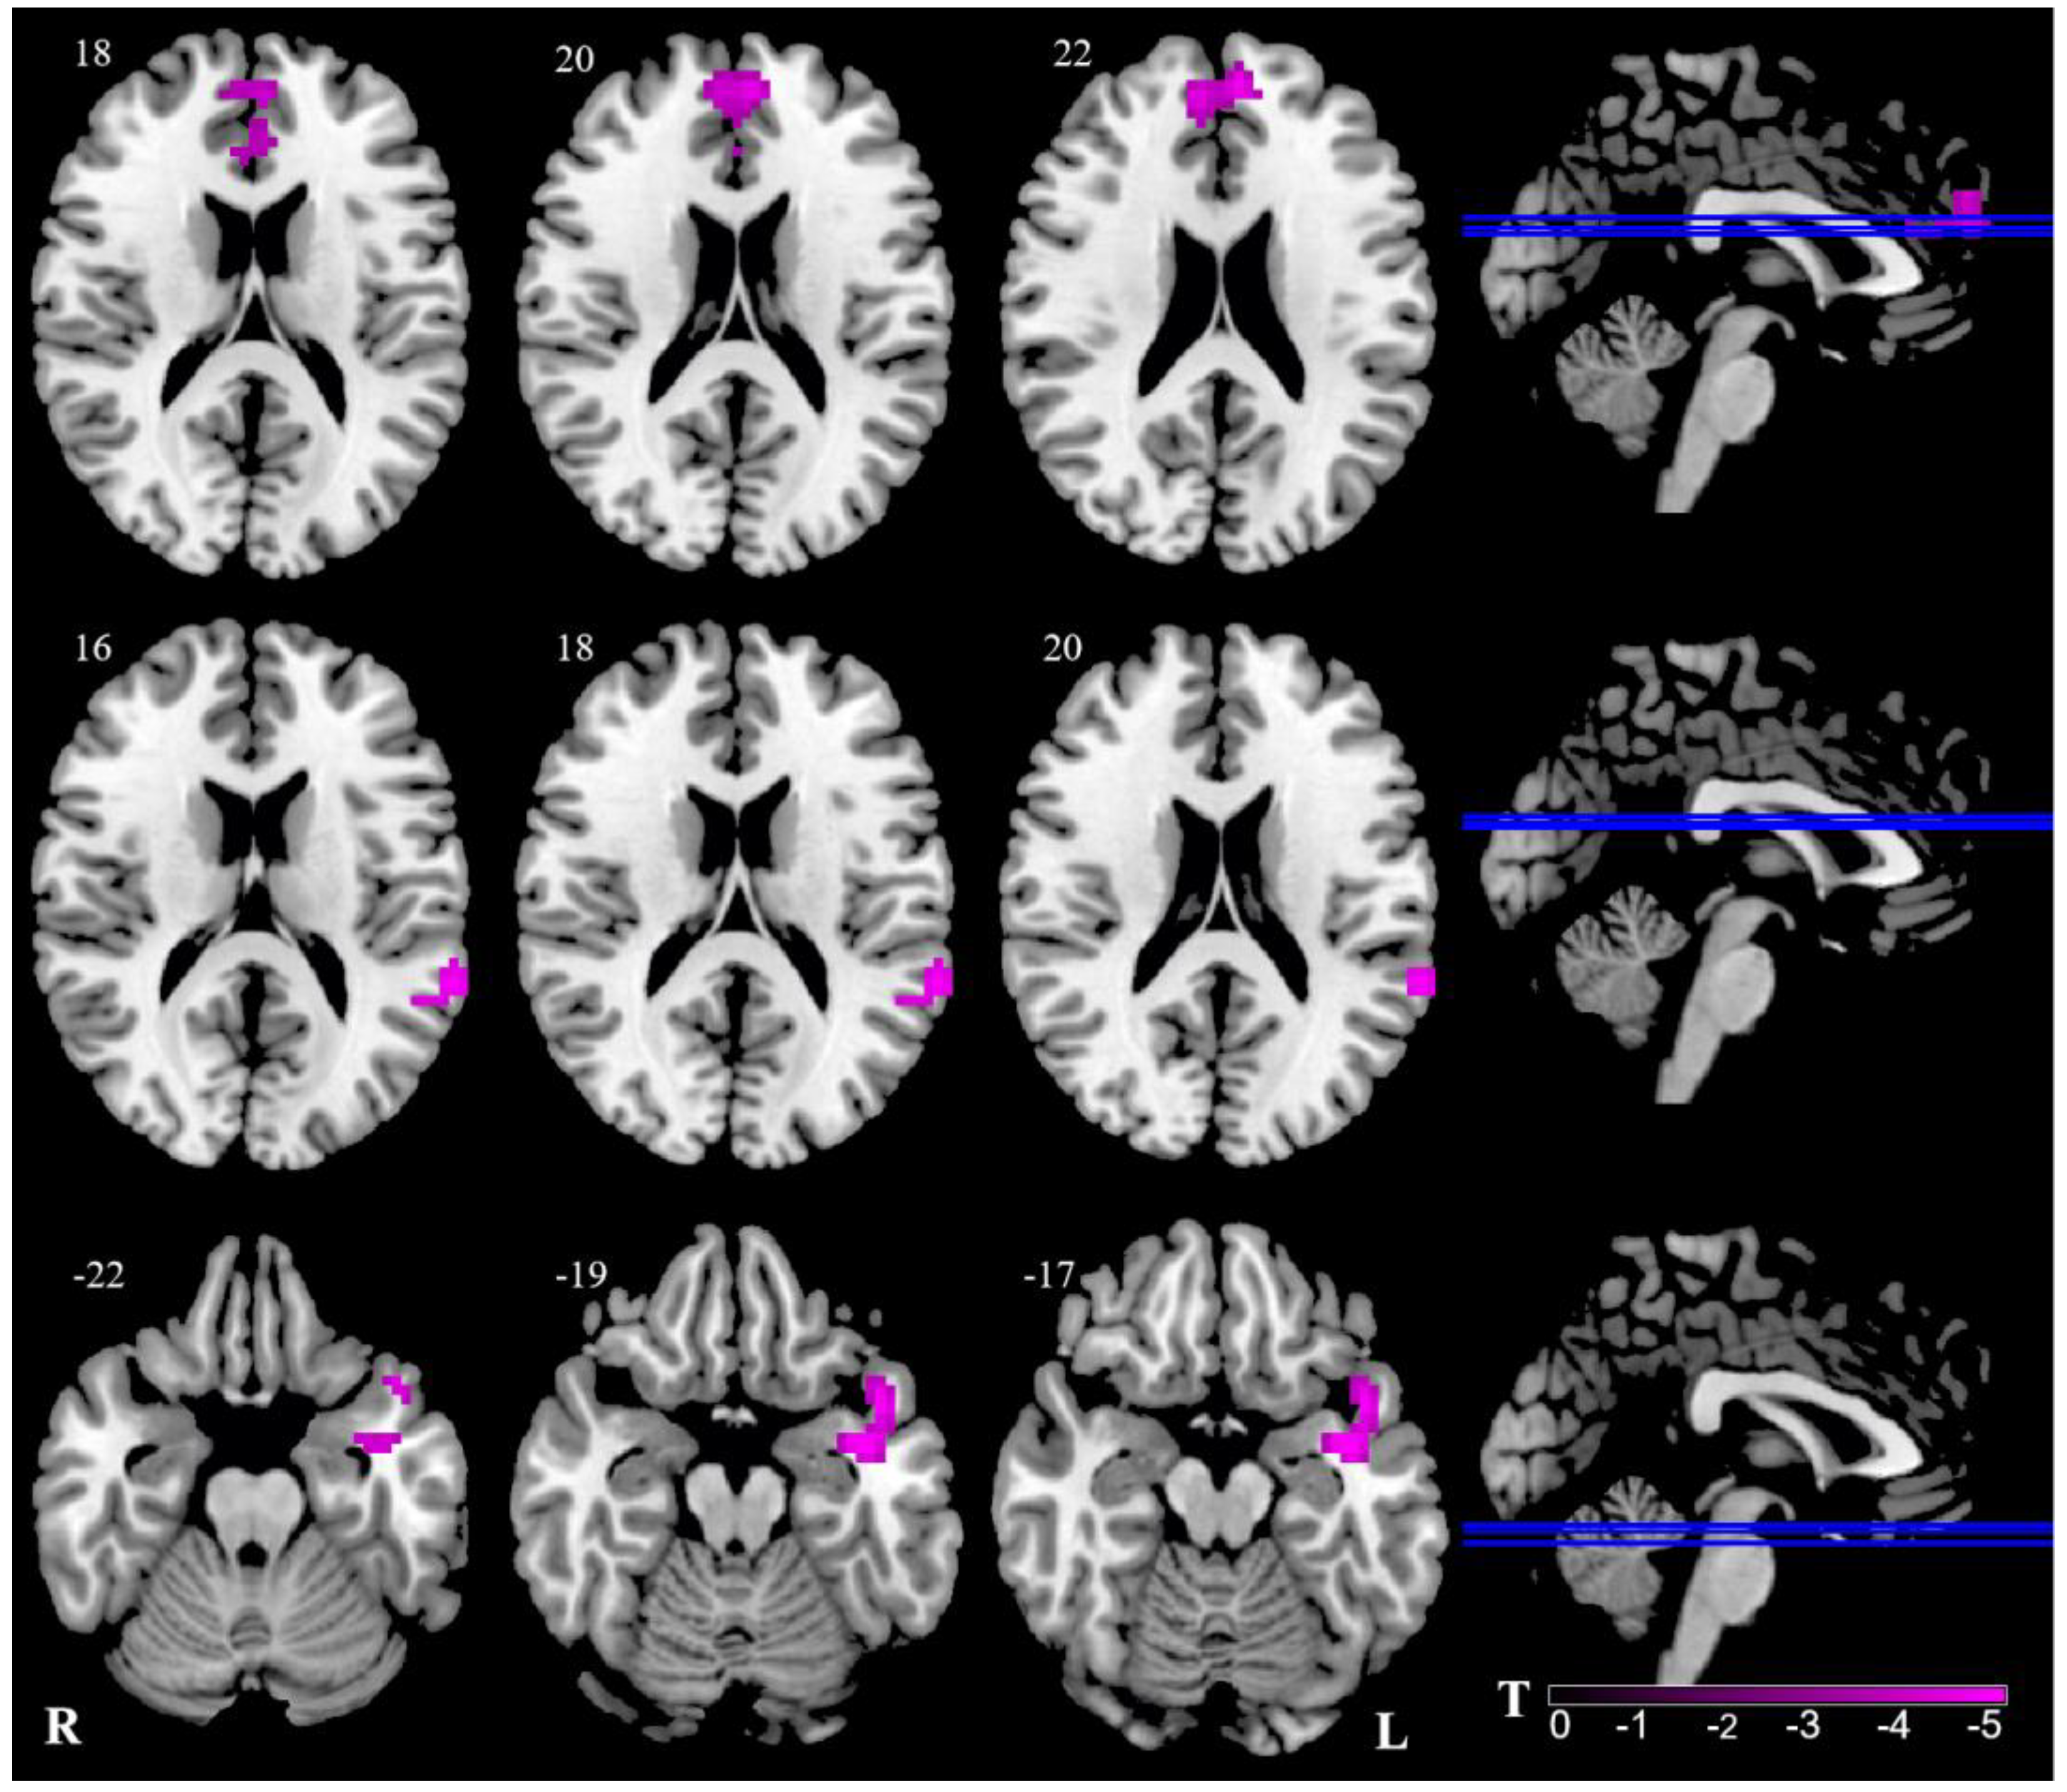

| Seed Points | Brain Regions | BA | Peak MNI | Cluster Voxels | T | |||

|---|---|---|---|---|---|---|---|---|

| x | y | z | ||||||

| L Thalamus | L | Medial prefrontal cortex | 9 | −6 | 54 | 27 | 74 | −5.36 |

| R | Medial prefrontal cortex | 32 | 7 | 52 | 26 | 64 | −5.36 | |

| L | Anterior cingulum cortex | 24 | −2 | 36 | 18 | 10 | −5.36 | |

| R | Anterior cingulum cortex | 32/24 | 5 | 48 | 22 | 15 | −5.36 | |

| L | Superior temporal gyrus | 42 | −63 | −42 | 19 | 58 | −4.25 | |

| L | Middle temporal gyrus | 21 | −51 | −48 | 3 | 66 | −4.25 | |

| L | Temporal pole | 38 | −42 | −3 | −18 | 58 | −4.86 | |